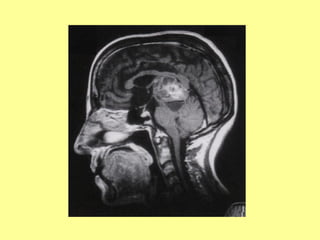

RNM de um paciente torporoso com hematoma subdural à esq.

RNM de umpaciente torporoso com hematoma subdural à esq.